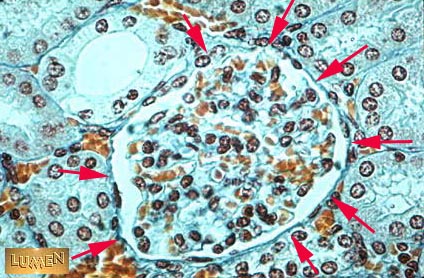

Answer 1

Glomerulus

Answer 2

RBC's, endothelial cells,

mesengial cells, podocytes